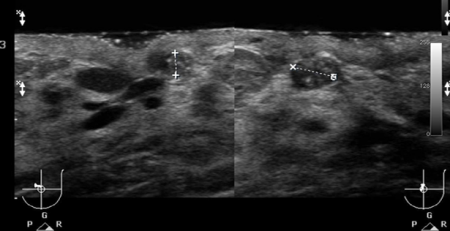

Oysa radyoloğun görevi ve sorumluluğu, sanılanın aksine cihazları kullanmak değildir! Kesin tanıya götürecek şekilde bir tıbbi durumu açıklamaya yönelik yöntemleri belirlemek, bunları en etkin şekilde kullanmak ve ortaya çıkarılan bulguları yeterli, doğru ve tedaviye yol gösterici şekilde yorumlamaktır. Hastasını bilgilendirmek ve yönlendirmek ise radyoloğun en başta hekim olmasından kaynaklanan doğal görevidir!

Cihazın nasıl ve ne kadar verimli kullanılacağı tamamen radyoloğun bilgi, beceri ve deneyimine kalmıştır. Yani diğer tıp dallarında olduğu gibi radyolojide de işi insanlar yapar, cihazlar değil! İşte bu nedenle radyolojide KALİTE, cihaz faktörü kadar insan faktörüne de bağlıdır.

Bilgi ve deneyim, uzun ve özverili bir süreçte kazanılır. Fiziksel ve ruhsal dayanıklılık, dikkat, sabır, titizlik gibi kişilik özelliklerinin ve günlük stres yükünün de insan faktörüne etkileri göz ardı edilemez.